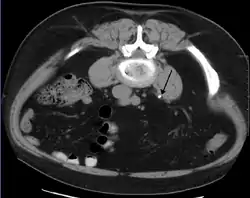

In people with a history of stones, those who are less than 50 years of age and are presenting with the symptoms of stones without any concerning signs do not require helical CT scan imaging.[49] A CT scan is also not typically recommended in children.[50]

Otherwise a noncontrast helical CT scan with 5 millimeters (0.2 in) sections is the diagnostic method to use to detect kidney stones and confirm the diagnosis of kidney stone disease.[13][47][51][52][7] Near all stones are detectable on CT scans with the exception of those composed of certain drug residues in the urine,[53] such as from indinavir. Calcium-containing stones are relatively radiodense, and they can often be detected by a traditional radiograph of the abdomen that includes the kidneys, ureters, and bladder (KUB film).[53] Some 60% of all renal stones are radiopaque.[51][54] In general, calcium phosphate stones have the greatest density, followed by calcium oxalate and magnesium ammonium phosphate stones. Cystine calculi are only faintly radiodense, while uric acid stones are usually entirely radiolucent.[55]

Ultrasound of the kidney can sometimes be useful, because it gives details about the presence of hydronephrosis, suggesting that the stone is blocking the outflow of urine.[53] Radiolucent stones, which do not appear on KUB, may show up on ultrasound imaging studies. Other advantages of renal ultrasonography include its low cost and absence of radiation exposure. Ultrasound imaging is useful for detecting stones in situations where X-rays or CT scans are discouraged, such as in children or pregnant women.[56] Despite these advantages, renal ultrasonography in 2009 was not considered a substitute for noncontrast helical CT scan in the initial diagnostic evaluation of urolithiasis.[52] The main reason for this is that, compared with CT, renal ultrasonography more often fails to detect small stones (especially ureteral stones) and other serious disorders that could be causing the symptoms.[11] A 2014 study confirmed that ultrasonography rather than CT as an initial diagnostic test results in less radiation exposure and did not find any significant complications.[57]